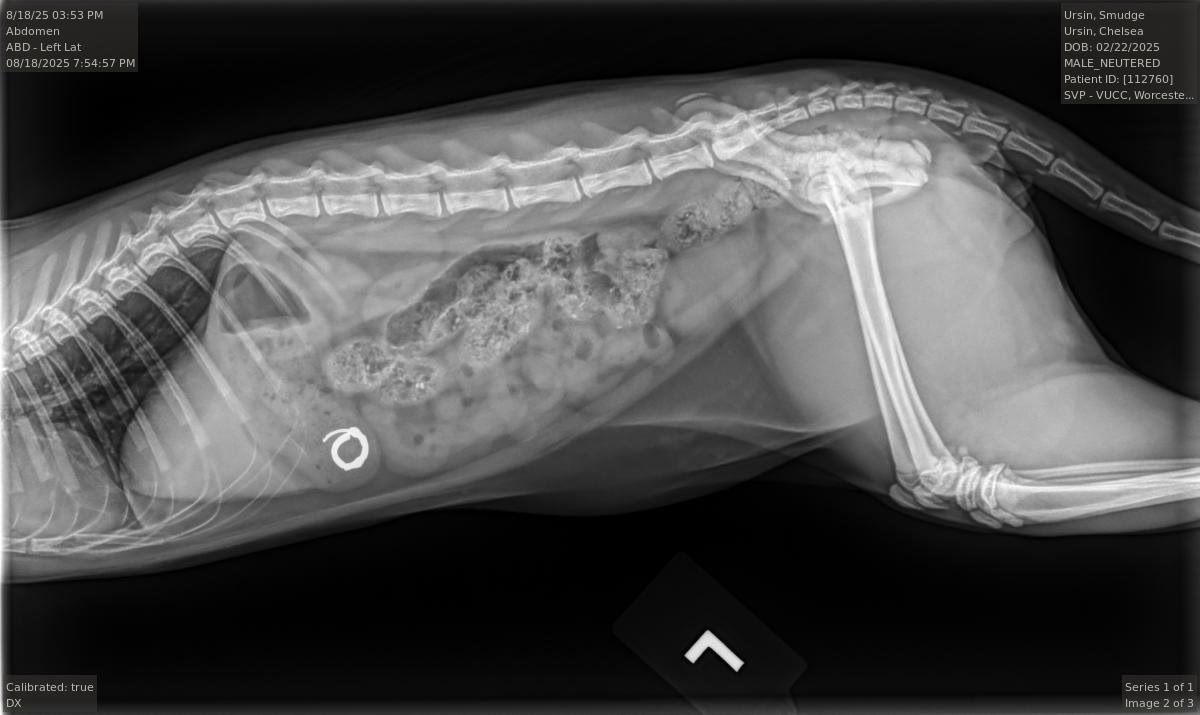

On the night of Sunday, August 17th, Smudge was cuddling with us in bed before we went to sleep. He started licking Chelsea's ear, and before she knew what had happened, he had somehow dislodged her hoop earring and swallowed it straight down his throat. After frantically checking the area around our bed and sifting through his poops the next morning, we took him to urgent care to get radiographs, and the results confirmed the worst. He had swallowed the whole earring, and it was currently resting in his stomach.

Today, August 20th, Smudge is at the Tufts Cummings School of Veterinary Medicine waiting to go under general anesthesia and have an endoscope put down his throat to hopefully remove the earring before it passes into his GI tract. Should it pass into his GI tract, a more invasive surgery may be required, and it could result in damage to his internal organs.